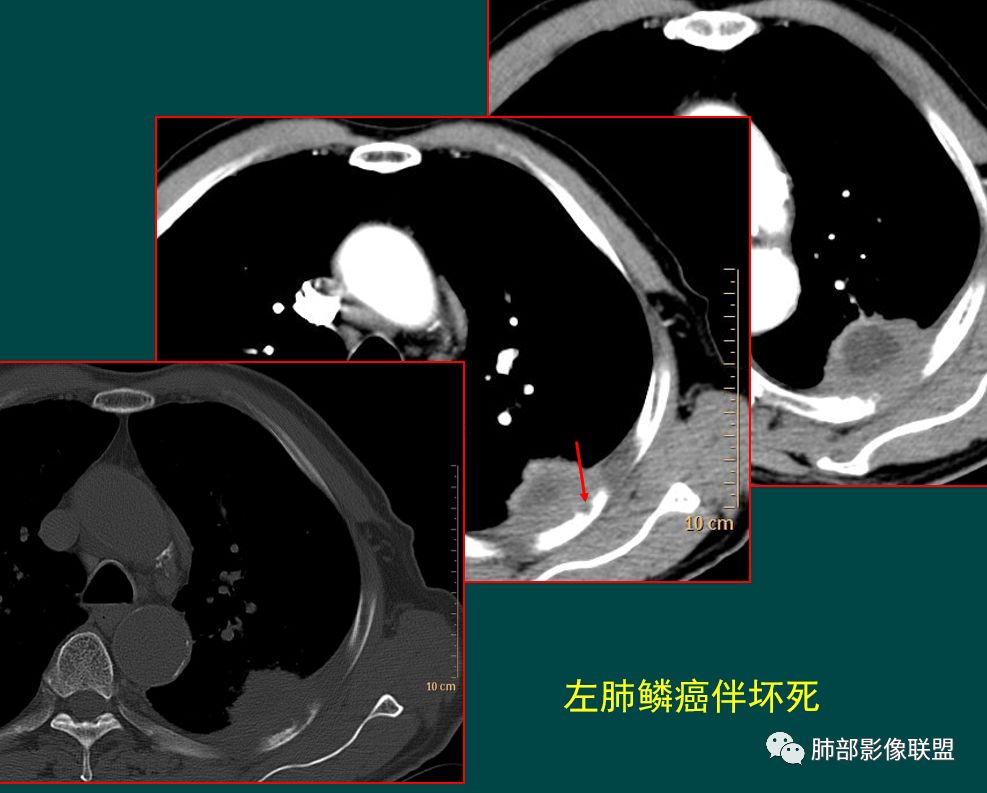

发生于肺边缘的小细胞癌有时会呈半圆形或圆冠状贴服于胸壁下,有老师称之为“山丘征”。经治疗后复查持续存在或增大的山丘影应当想到小细胞肺癌的可能性,尤其是在肺门纵膈淋巴结增大时。

位于胸膜下的鳞癌常与胸膜交成锐角

少数鳞癌、腺癌可类似山丘征,侵及相邻肋骨为其特点

一侧或双侧与胸膜呈钝角,但肋骨无破坏。

这个原发灶也不典型,但还是呈钝角。

多么经典的“馒头”。

鳞癌或腺癌等一般非小是这样的。

是山丘征吗?是小细胞癌吗?

对,不是,肋骨破坏了。

这个山丘破坏肋骨了,是鳞癌。

我至今还在寻找,位于胸膜下的小细胞癌,并且侵及肋骨的,似乎不是那么好找。

这个征象,归根结底还是回到病理,质地软,破坏力差。